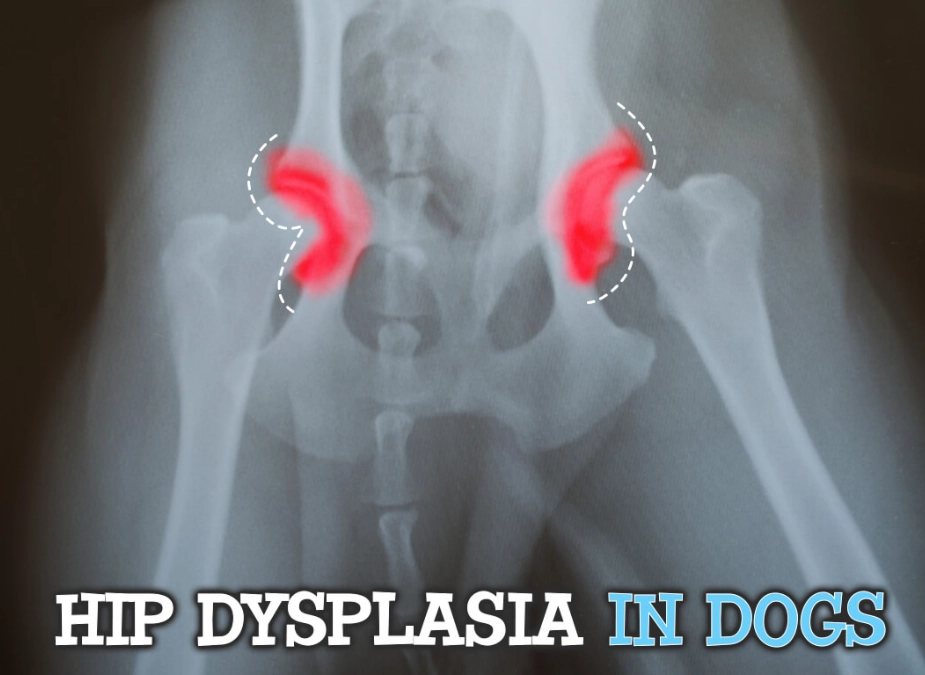

Let's break it down simply. A healthy hip is a ball-and-socket joint that fits together snugly. With hip dysplasia, the socket is too shallow, and the ball (the head of the femur) is loose. This poor fit causes abnormal wear and tear every time the dog moves. It's not just arthritis—arthritis is the result of the instability. The condition is primarily genetic, but factors like rapid growth, improper nutrition, and excessive exercise in puppyhood can worsen it.

- X-Rays (Radiographs): This is the gold standard. But not all X-rays are equal. A quick, awake X-ray often misses the true degree of laxity. For a definitive diagnosis, especially in young dogs, a hip-extended ventrodorsal view and often a PennHIP or Dorsal Acetabular Rim (DAR) view are needed. PennHIP, in particular, can detect laxity in puppies as young as 16 weeks, which is a game-changer for early intervention.